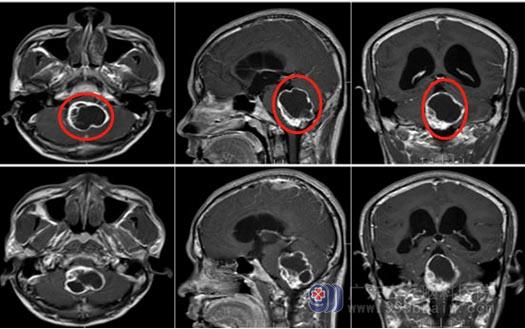

▲术前MR

小洪所患的很大可能是血管母细胞瘤,这是由脑神经和脊髓神经所产生的一种高度血管分化的良性肿瘤,血供非常丰富,手术中一旦出血,将会异常凶猛,难以控制,远非一般肿瘤手术可比,再加之小洪的肿瘤长在小脑和脑干中间,紧贴延髓,这是人体的呼吸中枢,万一损伤后果不堪设想,这无疑给手术又增加了一层难度。

医院副院长、神经外五科主任鲁明指示,患者为起源小脑蚓部突入四脑室的血管母细胞瘤,无家族史,腹部CT及全脊髓未见病变,考虑颅内单发病变。此肿瘤血管异常丰富,需要术前准确判断及术前的充分准备,更需要术中的精湛技术,才能避免大出血或切除不彻底情况。术后仍需注意再出血风险,同时肿瘤位置位于脑干背面,应尽可能避免脑干损伤,还要关注术后脑积水缓解情况。

手术尽管困难,但这是挽救病人的唯一希望,经过多次谨慎的病例讨论,决定先行术前栓塞,将肿瘤部分供血血管堵住,再行手术彻底切除。手术方案得到了小洪及家人的认可。术前栓塞顺利;手术按计划进行,打开颅腔后可见明显的较多供血动脉环绕肿瘤,虽然做了部分栓塞仍存在较多血管,肿瘤位于脑干的背面,瘤体紧贴延髓;先游离肿瘤周边供血血管,并使用动脉瘤夹阻断必要的动脉,同时保护好重要的引流静脉,游离阻断血管后再逐步将肿瘤完整剥离,肿瘤大小4.8cm×4.8cm×5.2cm,脑组织及血管保护良好,完美地避免了大出血,术中出血约150ml。病理结果证实了肿瘤为血管母细胞瘤。